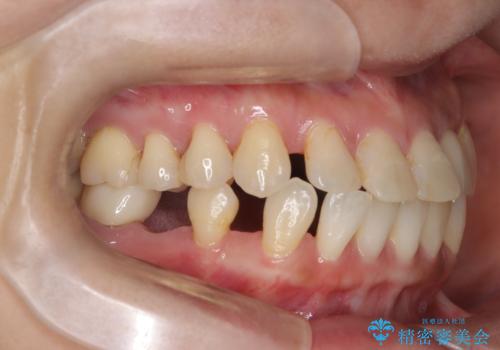

- 歯と歯の間に大きなスペースがある「空隙歯列(すきっ歯)」と、一部の歯が欠損していることによる噛み合わせの不安定さを主訴にご来院されました。

精密検査の結果、全体の隙間を閉じるだけでは適切な咬合バランスが得られないため、まずはインビザラインを用いて歯の位置を理想的な場所へと整える計画を立案しました。矯正によって欠損部位に適切なスペースを確保した後、その部分にインプラントを埋入することで、審美性と機能性の両立を目指しました。